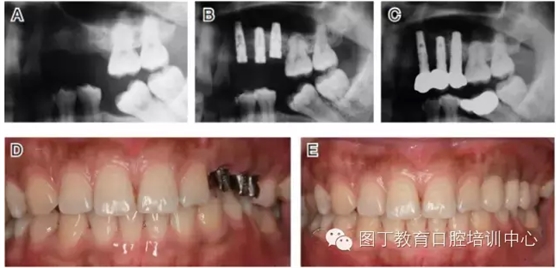

病例9 種植體進(jìn)入額竇腔內(nèi)(圖11)

圖11

④種植體植入上頜竇或其他竇腔的情況較少見,但可能在患者為Ⅳ類骨或骨量少時(shí)發(fā)生,5~6mm骨量時(shí)也可能發(fā)生(如圖11所示)。